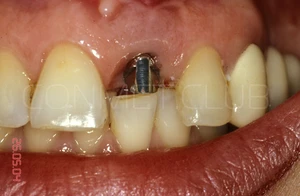

Имплантат установлен и зафиксирован винт-заглушка. Обратите внимание, что даже при столь широком экваторе имплантата не удалось полностью перекрыть диаметр костной альвеолы в направление зуба 11. Швы не накладывались и поверхность имплантата закрывалась мазью Солкосерил Дентал

В этот же день была изготовлена провизорная коронка крепившаяся к соседним зубам на стекловолоконную ленту и композитный цемент.